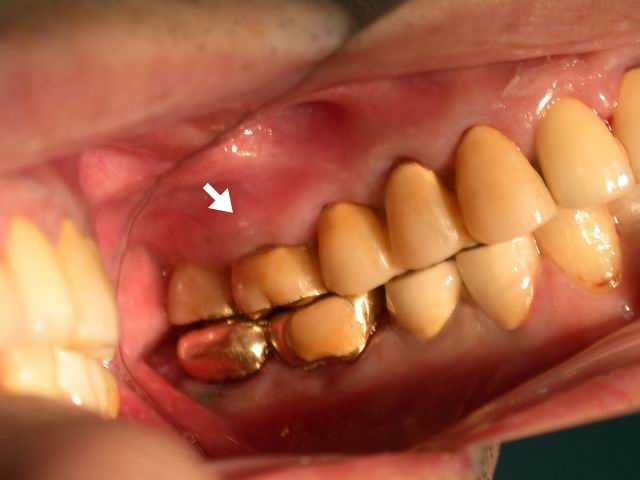

上圖例為一動搖膿牙、牙根分叉處骨脊腐毀成一坑穴,藏腐。

AA乃幾乎所有牙醫都一致認為應該要拔除 而後再植牙 或磨損兩邊好牙 做套死的牙冠、牙橋。因為BB的根叉腐穴 以目前一般療法 無法作完全徹底的治療。經新法New Taiwan Konus分切牙根的牙周治療法 加Rest Arm具備分力活套冠修復法 得以完全治癒 而留存 並長保功能。

AA乃幾乎所有牙醫都一致認為應該要被拔除 而後植牙,或磨損兩邊好牙 再做套死的牙冠、牙橋。因為BB根叉腐穴 以目前一般療法 無法作完全徹底的刮除治療。經新法New Taiwan Konus分切牙根的牙周治療法 加上新設計的Rest Arm具備分力活套冠修復法 得以完全治癒 而留存 並長保健固功能。